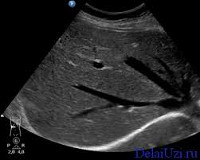

Ультразвук печени позволяет ребенку визуализировать паренхиму органа, общую желчь и общие печеночные протоки, анатомические структуры дверей печени. Во время исследования обращают внимание на размеры левой и правой долей, контуры печени, эхоструктуру, сосудистую модель; расчетный диаметр воротной вены, внутрипеченочных протоков и общего желчного протока; установлены взаимосвязи печени с соседними органами - желчным пузырем, правой почкой и поджелудочной железой. Ультразвуковая картина может выявить изменения в печени, вызванные гепатитом, болезнью накопления гликогена, сердечной недостаточностью, муковисцидозом, паразитарными заболеваниями, опухолями, повреждениями брюшной полости При подозрении на гемангиомы сосудистые нарушения проявляются в допплеровском сосудистом сосуде печени.

Во время теста оцениваются следующие параметры: топография органа, передне-задние размеры правой и левой доли печени, контуры, структура паренхимы, эхогенность печени; диаметр воротной вены, общий желчный проток, печеночные вены, состояние внутрипеченочных желчных протоков. В режиме ЦДК исследуется состояние кровотока в сосудистой сети печени. Эти показатели могут значительно различаться, учитывая возраст ребенка, поэтому специалист по УЗИ печени должен знать и учитывать возрастные нормы. Эхоскопическими признаками патологии могут быть рост печени, неоднородная эхоструктура, неровные края, повышенная эхогенность, увеличение диаметра кровеносных сосудов, наличие очаговых поражений.